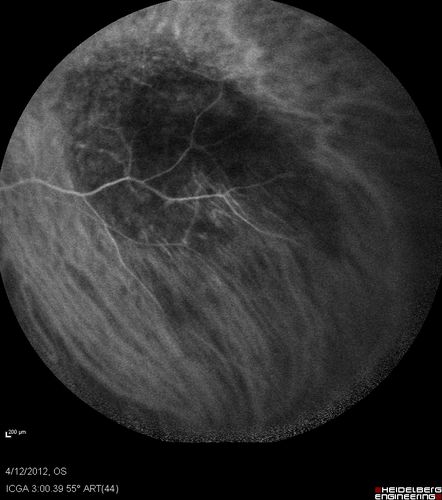

Medium Choroidal Melanoma Left Eye

Melanoma - Choroidal Medium - Macular